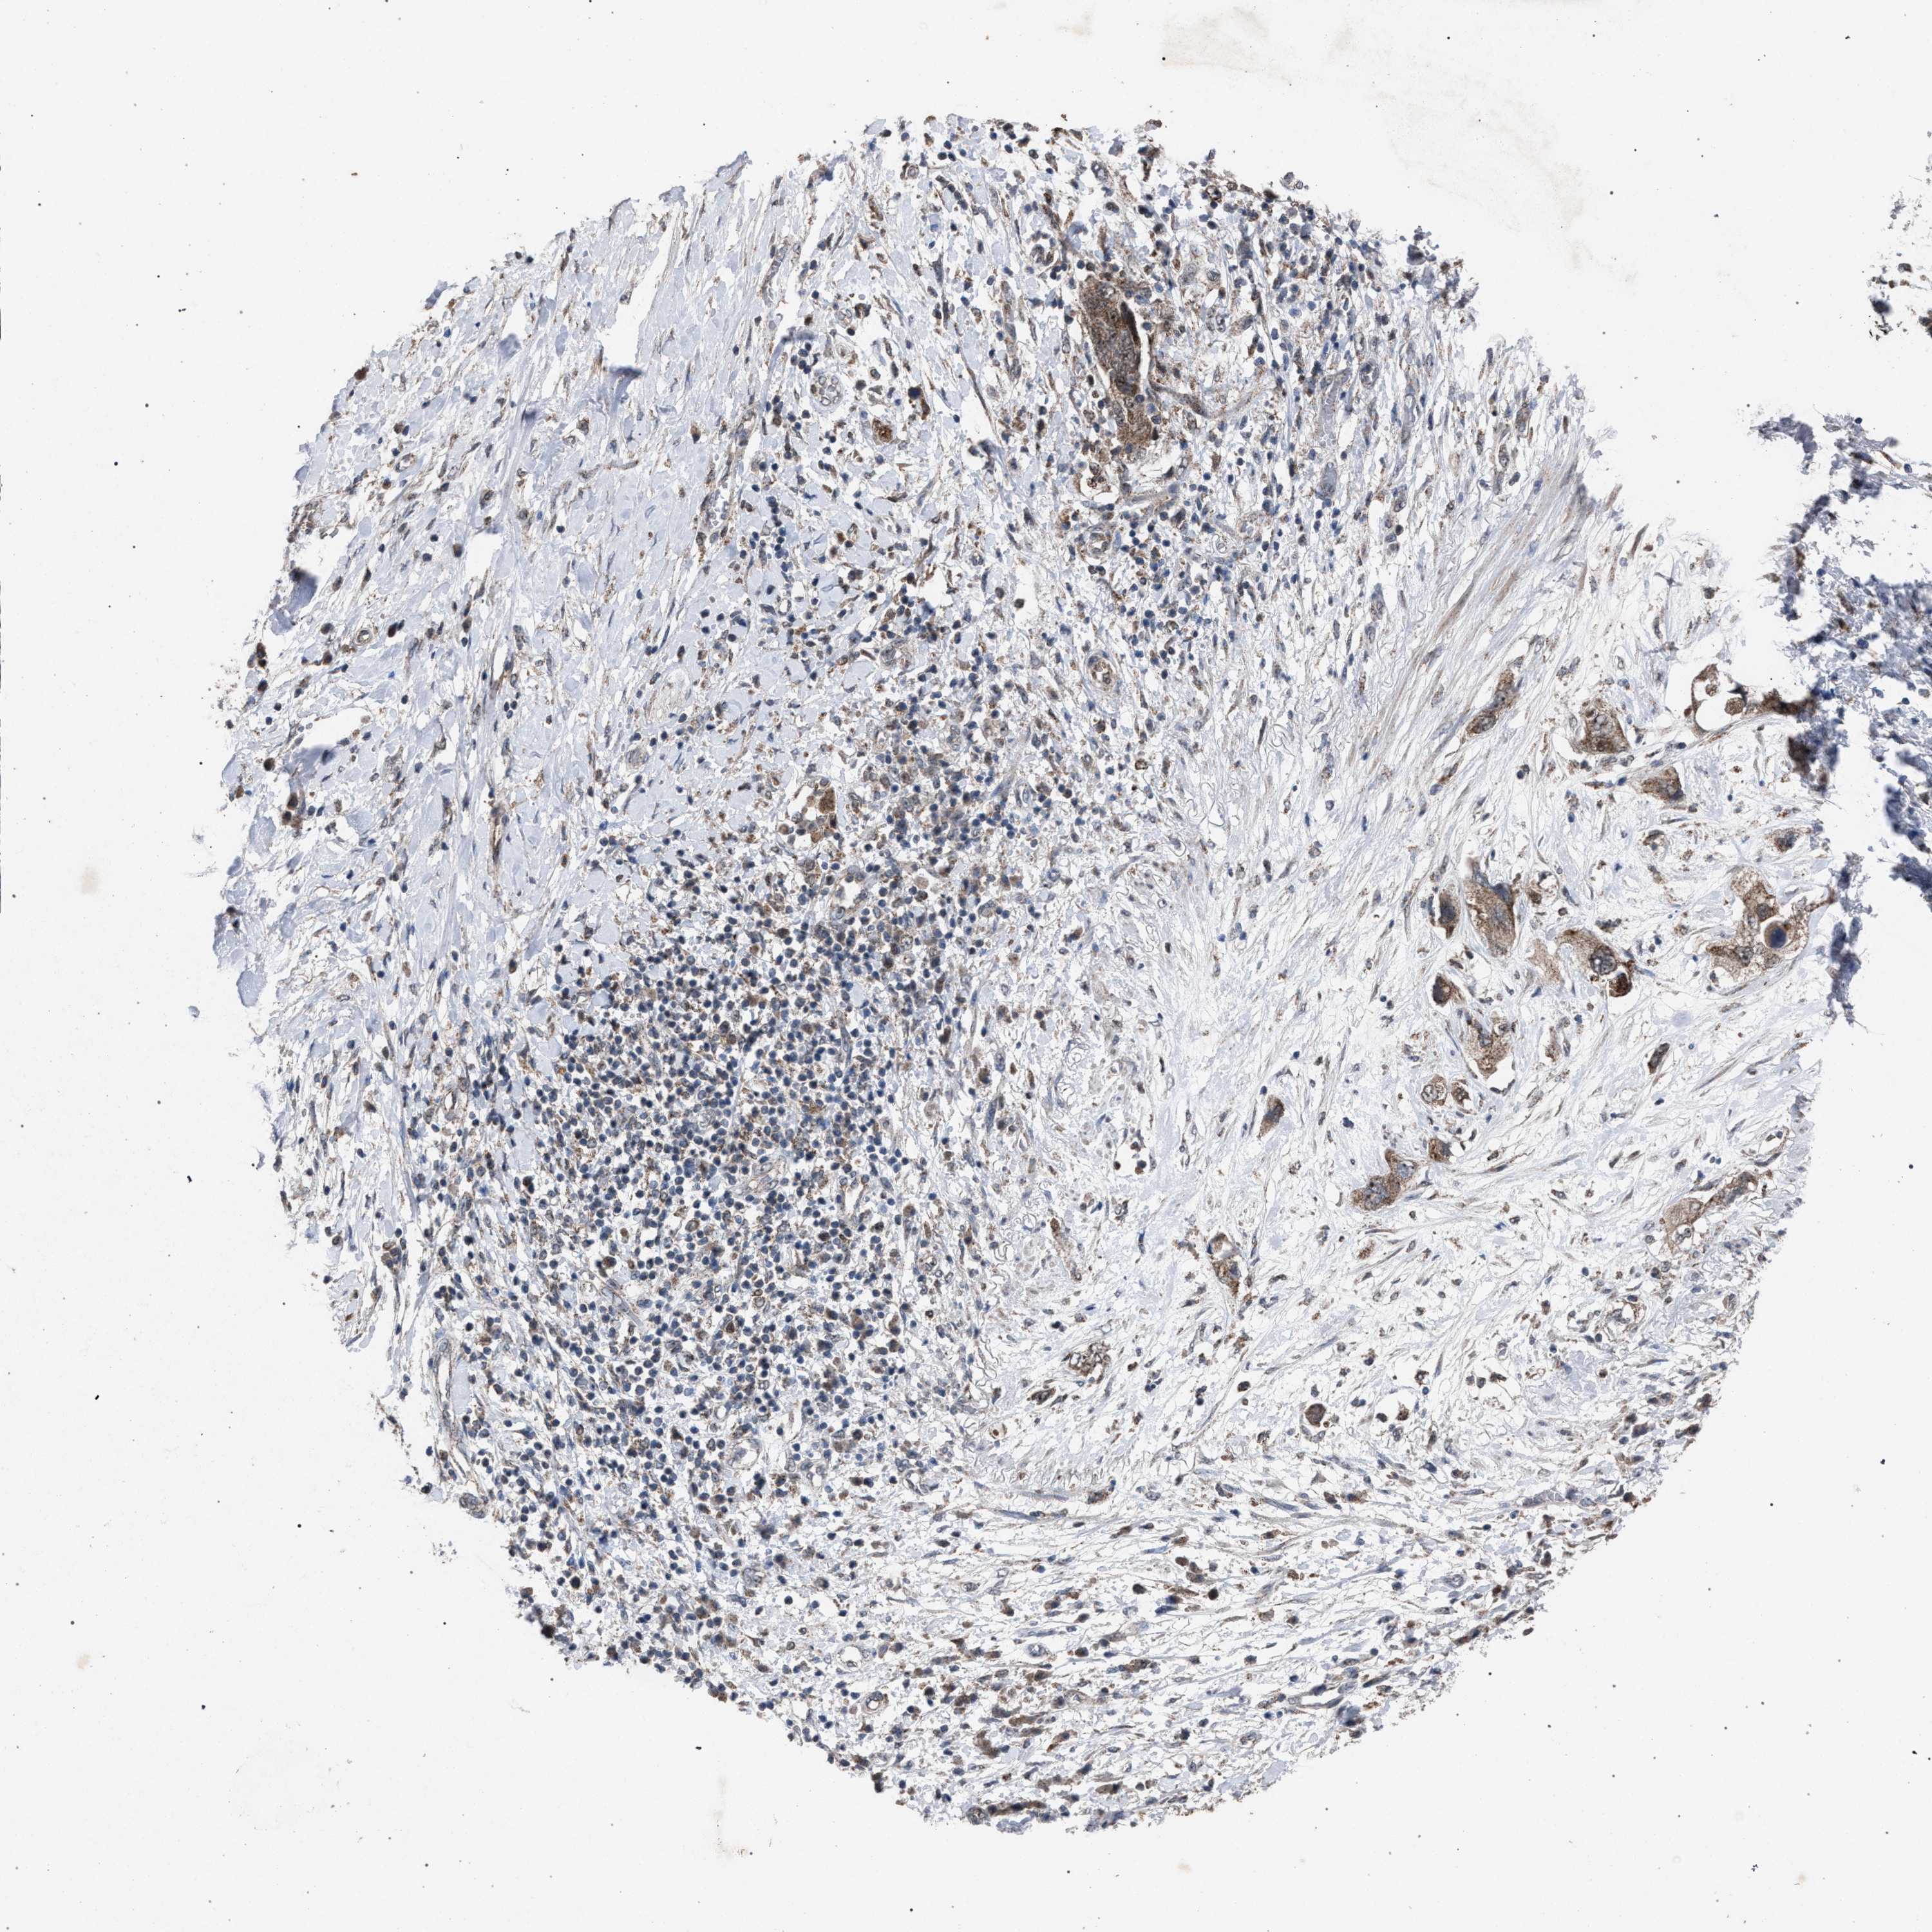

PANCREATIC CANCER - Protein expressioni

A mouse-over function shows sample information and annotation data. Click on an image to view it in a full screen mode. Samples can be filtered based on level of antibody staining by selecting one or several of the following categories: high, medium, low and not detected. The assay and annotation is described here.

Note that samples used for immunohistochemistry by the Human Protein Atlas do not correspond to samples in the TCGA dataset.

Antibody stainingi

Antibody staining in the annotated cell types in the current human tissue is reported as not detected, low, medium, or high, based on conventional immunohistochemistry profiling in selected tissues. This score is based on the combination of the staining intensity and fraction of stained cells.

Each image is clickable and will lead to virtual microscopy that enables deeper exploration of all samples and also displays staining intensity scores, fraction scores and subcellular localization as well as patient and tissue information for each sample.

Antibody HPA021302

Antibody HPA021311

Antibody HPA021479

Adenocarcinoma, NOS